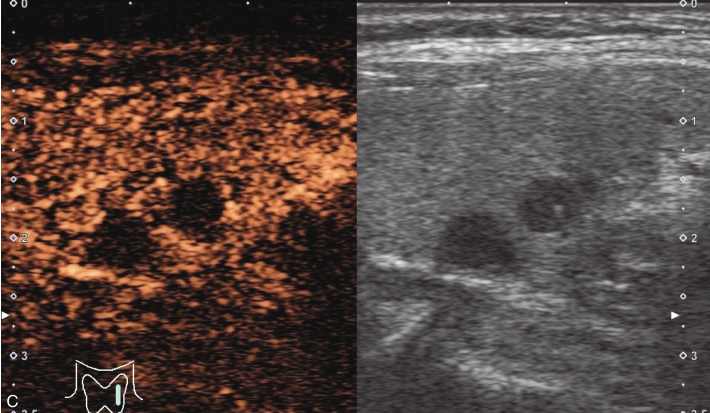

甲状腺左叶下部见一低回声结节,边界清,形态尚规则,内见多发斑状强回声,后方伴声影,CDFI内未见明显血流信号,见图1-3-16。

注入造影剂后结节内实性部分大部分呈无增强,其周边可见少许点状造影剂灌注,结节边界清,形态较规则,周边甲状腺被膜完整,见图1-3-17、ER1-3-8。

(1)结节内部呈无增强或低增强。

(2)结节边界清晰,形态较规则。

(3)结节周边被膜连续完整。

甲状腺“木乃伊”结节既往常规超声多表现为囊实混合性回声,边界清晰,经过一段时间后,结节萎缩塌陷,呈实性低回声,部分内有钙化。超声造影结节内部多呈无增强或低增强,呈低增强时则难与乏血供的甲状腺恶性肿瘤鉴别,鉴别要点为超声造影“木乃伊”结节与腺体分界较为清晰,无被膜浸润征象,且需要结合既往常规超声检查及动态随访。

图1-3-16 甲状腺“木乃伊”结节常规超声声像图

A、B.甲状腺左叶纵切面示甲状腺左叶下部低回声结节,边界清,形态不规则,内可见多发斑状强回声;C.CDFI血流图示结节内未见明显血流信号。

图1-3-17 甲状腺“木乃伊”结节超声造影图

A.注入造影剂后16s图像;B.注入造影剂后42s图像